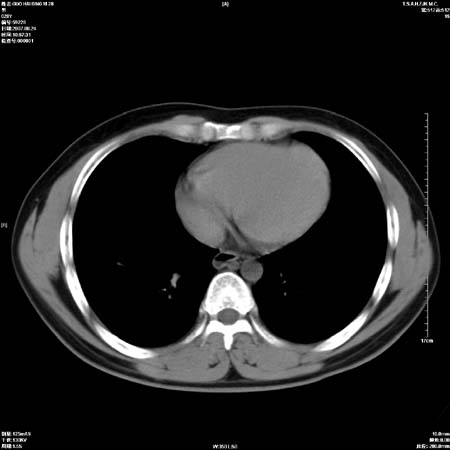

左肺门区软组织肿块,左肺上叶支气管开口消失,纵隔内见肿大淋巴结,考虑左中心型肺部,可以做纤支镜取病理确认.

左肺肺门区肿块影,分叶明显,左肺上叶支气管开口受压,纵隔内见肿大淋巴结,考虑左中心型肺癌。

支持左上叶中央型肺癌伴纵隔淋巴结转移.

左上叶中央型肺癌伴纵隔淋巴结转移

肿块形态影像支持左上叶中央型肺癌伴纵隔淋巴结转移。

左肺门区分叶状软组织肿块,纵隔内有肿大淋巴结,诊断肺癌应该问题不大。

左肺中心型肺癌并纵隔淋巴结转移!考虑为小细胞肺癌,没有手术机会了,只能进行放化了,疗效不错,但极易复发。没办法,现在肿瘤年轻化越来越明显了。